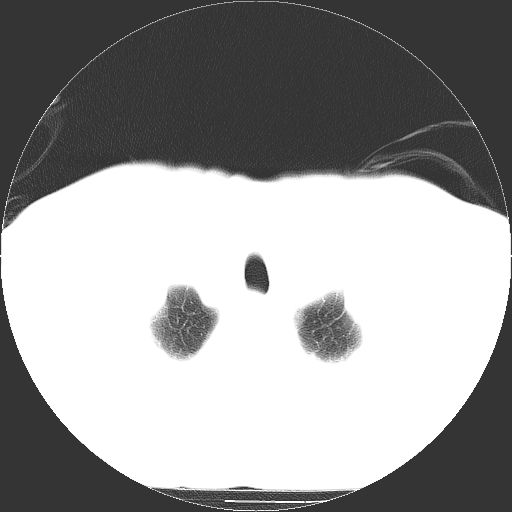

标题: CT21804:男,65岁,咳嗽、咳痰、发热5天。 [打印本页]

男,65岁,咳嗽、咳痰、发热5天。

慢支,肺心病

支持慢性支气管炎伴感染,双侧少量胸腔积液.

两肺间质纤维化,支扩合并感染,双侧胸腔积液

慢性支气管炎并感染,支扩,双侧少量胸腔积液.